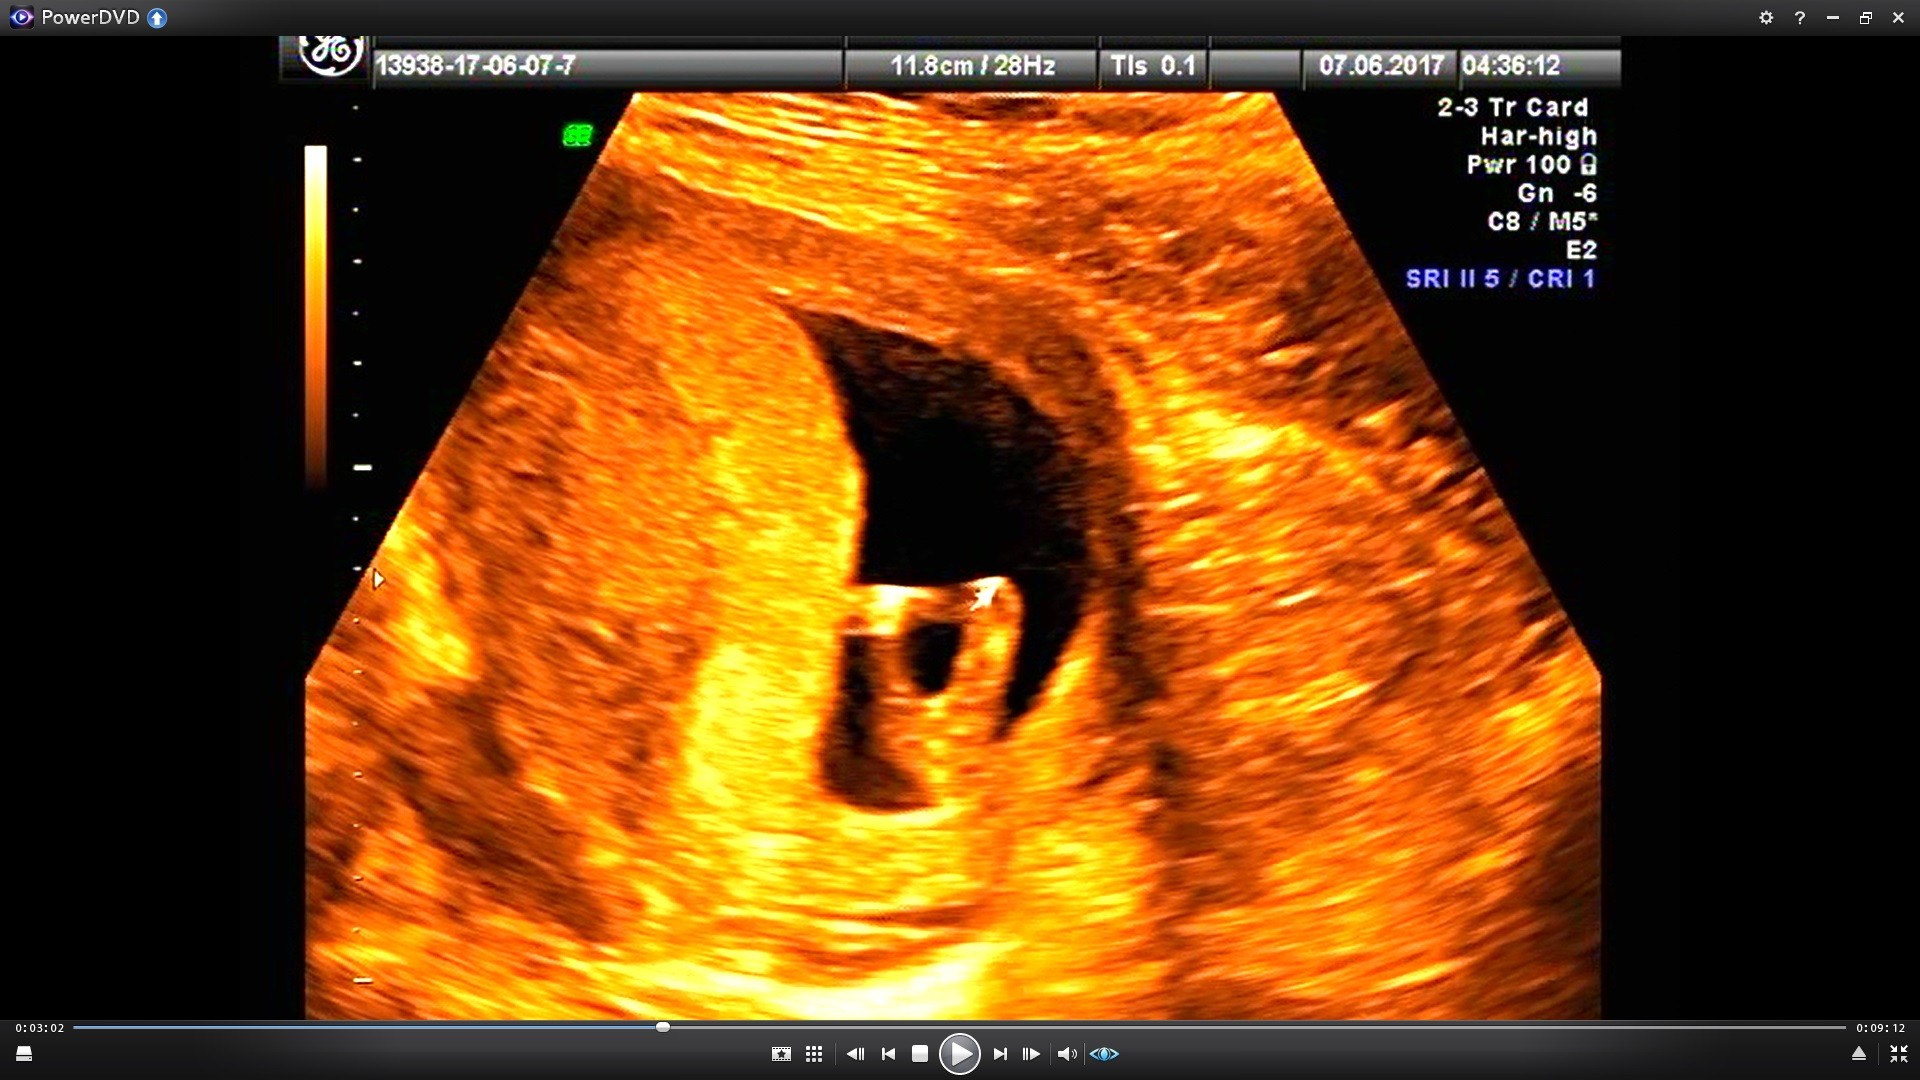

Wszystko dobrze, dzidzius ma juz 5,2 cm, nie szlo go zmierzyc, caly czas machal raczkami i nóżkami i uwaga..pokazal nam sisiorka :D czyli bedzie chlopak! :-) Mąż przeszczesliwy, ja jeszcze troche przerazona :P

Tutaj moj szkrab w calej okazalosci, na drugim nozki podciagnal do gory i tez w calej okazalosci pokazal malego sisiorka ;)